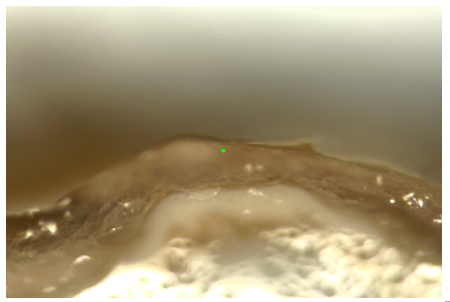

Hình 5. Hình ảnh mô da cố định formalin quan sát dưới kính hiển vi quang phổ Raman, vật kính 10x.